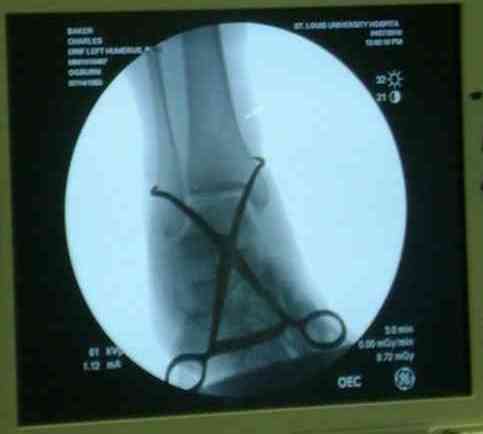

Впечатления об американской ортопедии. По проторенной коллегами дорожке в апреле по приглашению доктора Кульджанова Д., мы, 2 врача из казахстанской провинции -Канат Тезекбаев и Чертковер Григорий \ака Антон Андрианов\ провели 2 недели в университетской клинике города СентЛуис, Миссури. В прошлом году Никита Заднепровский, ранее побывав там, писал на форуме свои впечатления. Не желая повторяться, хочется довести до сведения коллег малую часть того, что нас поразило в США. Хотя одному из нас довелось поучиться три месяца в ФРГ по гранту АОАА и видеть клиники Швейцарии увиденное было ошеломляющим. Во-первых, подготовка врачей ортопедов длится 5-6 лет после колледжа, рабочая неделя их длится до 80 часов в неделю .Они –резиденты, закрывают все дежурства, прием пациентов. Опытные их учителя вызываются в ночное время по графику и очень многое резиденты делают сами под их контролем. Через пять лет к 33-35 годам он выходит самостоятельными врачами и ищут себе высокооплачиваемое место работы. Все стационары и амбулаторные приемы, частные или управляются частными компаниями, вся хирургическая служба высокодоходна и с врачами очень считаются, особенно по части приобретения заказанной ими техники. Экономическая целесообразность оставляет врачу только труд его квалификации, выписки, например, он диктует по телефону, мылом они летят в Индию, где дешевле труд машинистки, а к утру они уже в печатном виде у него в компьютере. Библиотека департамента ортопедии заставила утереть слезы доброй зависти, как и стопки журналов со всего мира на столе у профессора Кульджанова. Отсутствуют пленки рентгенограмм, доступ к сети с любого ПК, где хранятся все исследования пациента от поступления до амбулаторного этапа, интернет -до операционной. Удивительно крепок их командный дух, все дружно радуются быстро и удачно сделанной операции, бегут смотреть, что творится у коллеги, могут помыться на короткий момент для помощи и изучения, после идти продолжать свою работу. Еженедельные занятия с резидентами держат в информационном тонусе всех врачей. Можно много писать о работе приемного отделения, но те, кто видел сериал ER\Скорая помощь\ могут не сомневаться – на одного поступающего накидывается толпа врачей и персонала, а количество снимков и сканов МРТ и КТ не укладывается в наших головах. Правда о фильме они отзываются с иронией- фикшн, любовь на работе не крутим! Непререкаемый авторитет в клинике нашего куратора Джолдаса Кульджанова позволил нам свободно перемещаться по оперблоку и снимать операции. Активная хирургическая тактика при лечении политравмы, а именно таков состав пациентов, операции на нескольких сегментах позволяют избежать осложнений даже у престарелых . Так с д-ром Кулиджановым мы приняли участие в остеосинтезе перелома шейки, тибиального плато и предплечья у 92-летней дамы с протезом клапана, живущей на антикоагулянтах непрямого действия. Для выполнения операции анестезиологами путем переливания свежей крои и плазмы было создана на пару часов окно и операция была практически сухой. Вообще анестезиологи не выпячивают свою роль и с пониманием относятся к задачам ортопедов, вспоминается перл Илизарова- не больной для анестезиолога, а врач для больного\1982 год Курган\. Очень понравилась великолепная хирургическая техника всех докторов, крайне бережное отношение к тканями, практически не видели работы распаторами, минимально оголяется кость, используется инструментарий ЛОР и нейрохирургов. Орошение ран, джет- лаваж инфицированных ран проводится только физ.раствором. Многолетние наблюдения доказали состоятельность и даже к перекиси относятся критично -жжет ткани. ЭОП светит постоянно, даже измерение длины винта контролируется визуально, в их лексиконе нет слова СОЙДЕТ!Нет слов благодарности для Джолдаса, который опекал нас, как неразумных птенцов, часами сидел с нами перед монитором, ломая наши установки и пробивая косность совкового мышления. Те, кто уже бывал у него в гостях запомнили удивительный симбиоз полного западника с широкой восточной душой. Прилагаю несколько примеров изящной работы ортопедов из СентЛуиса.В первом случае у политравмированного пациента под ЭОП динамической пробой верифицирован разрыв МБС и выполнена фиксация позиционными винтами, 3.5 кортикальными.Кстати метчика в работе мы не видели, все винты self taping.Во втором случае у пациента с открытым многооскольчатым переломом дистального плеча на 4 сутки выполнен остеосинтез. Обратите внимание =доступ без резекции олекранона,медленная и ювелирная работа нетипичным для нас инструментом закончена полным восстановлением анатомии локтевого сустава.В небольшой дефект залит БМП\OP-1 Stryker ,продукт роста клеток человека в генной модификации\. Для профилактики гетеротопической оссификации ряд врачей применяют облучение на 2-3 сутки .Предвижу реплики скептиков - нам бы их зарплаты и оснащение, мы бы! Но для начала нам бы их учителей, их командный дух и их разумных рациональных организаторов!